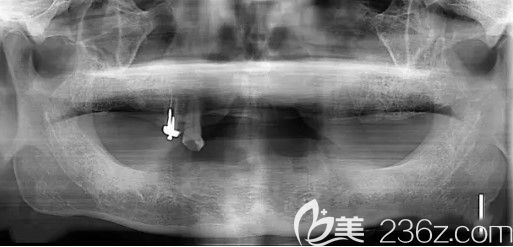

【我種牙前的 CT片,全口牙缺失,醫(yī)生說我骨量不足】:

來天津中諾口腔醫(yī)院,孩子們找的是張喜明醫(yī)生,經(jīng)過檢查,醫(yī)生說我的牙槽骨萎縮了,和孩子們商量后,決定的種牙方案是——立得用種植體系。